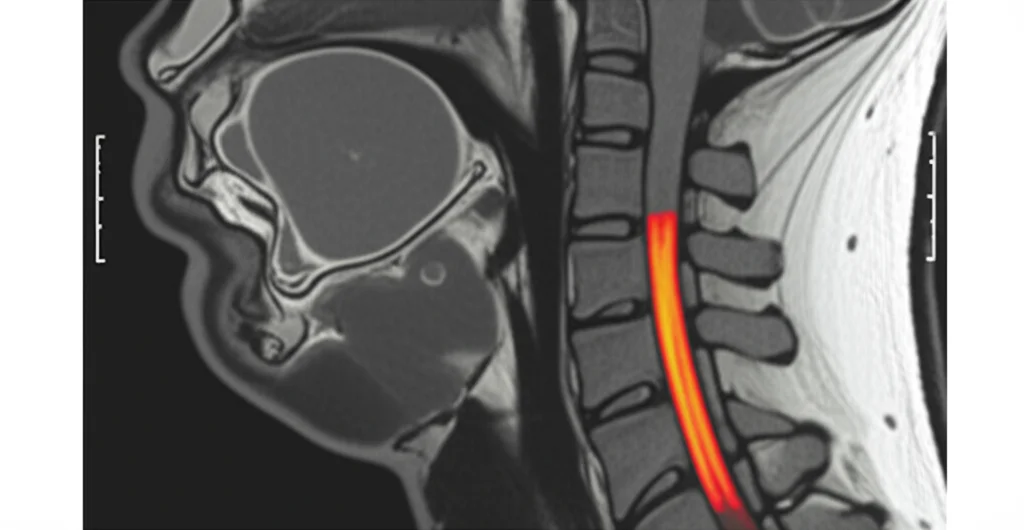

Qui entra in gioco la Risonanza Magnetica (RM). Questo esame più sofisticato è in grado di “vedere” direttamente il tessuto molle del midollo spinale e può rivelare lesioni, edemi (gonfiori) o piccole emorragie che le radiografie e la TAC non riescono a catturare. Quindi, la diagnosi di SCIWORA si basa sui sintomi clinici e sulla conferma tramite RM, in assenza di danni ossei evidenti agli esami tradizionali.

Lo studio conferma che il tratto cervicale (il collo) è di gran lunga il più colpito (99% dei casi!). I livelli specifici più frequentemente interessati erano C4 e C5. Questo ha senso, perché il collo è la parte più mobile e forse meno protetta della colonna. Solo un caso riguardava il tratto toracico.